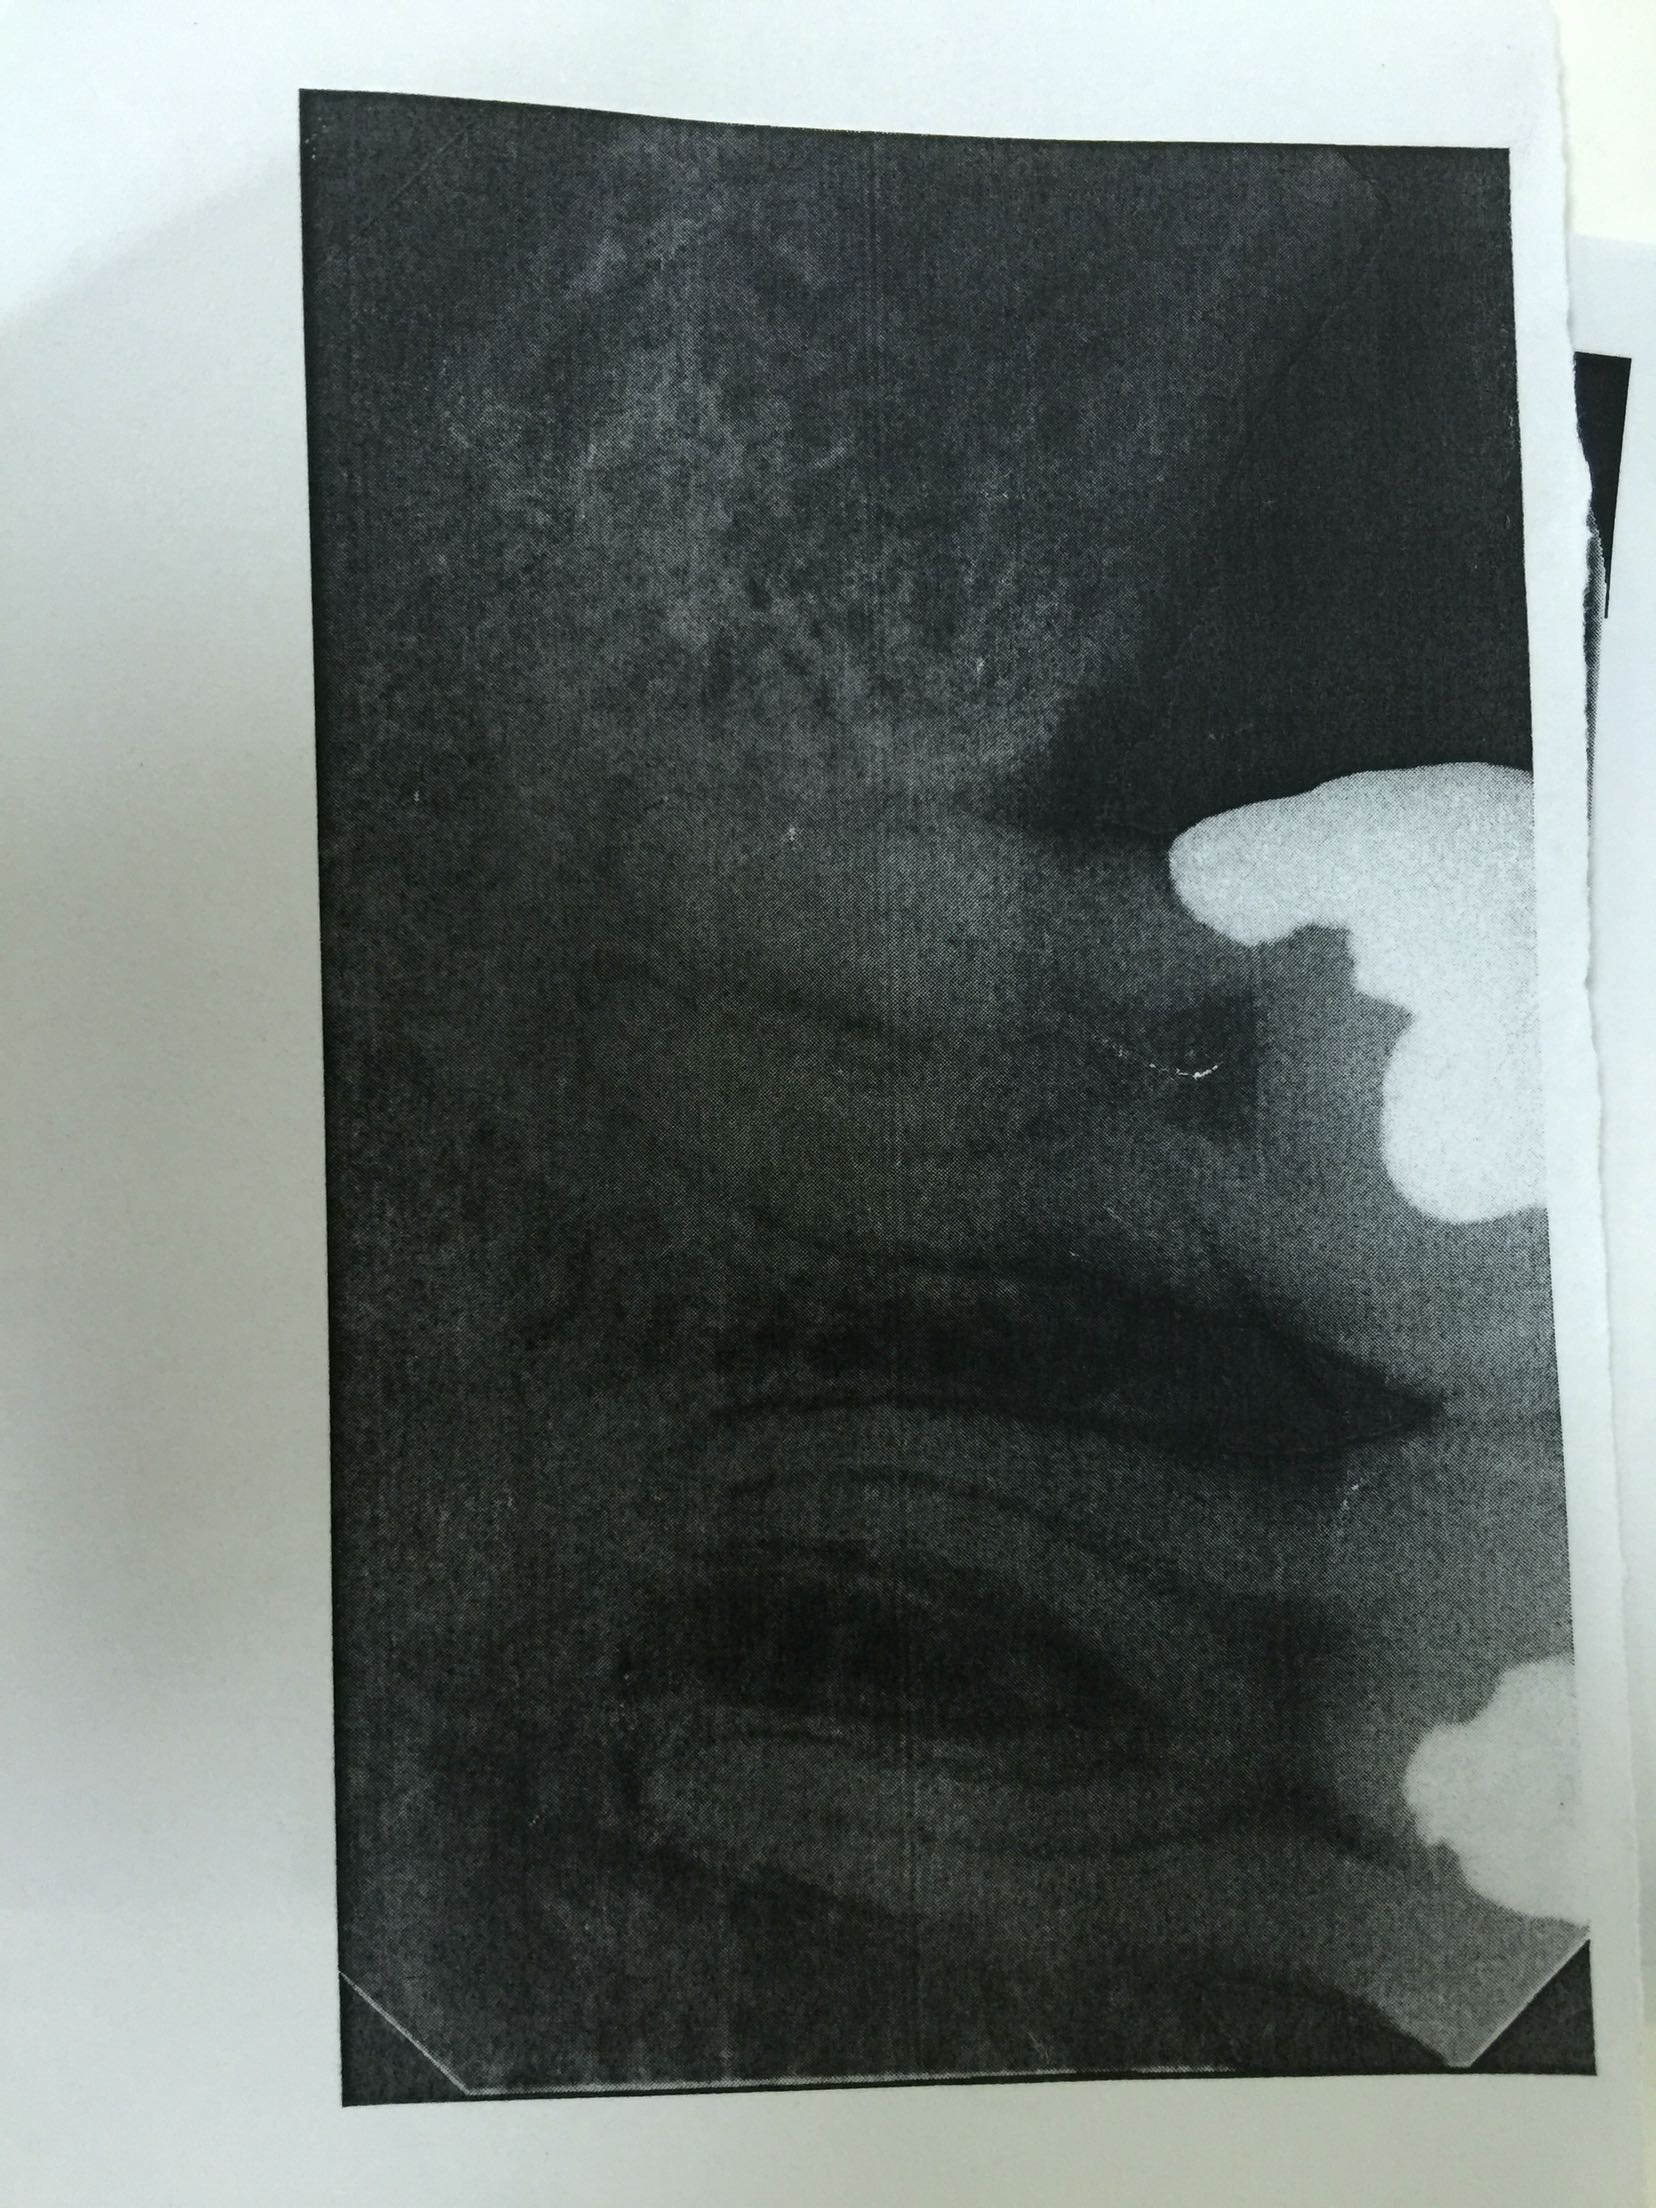

检查:47远中邻合面充填物存,叩诊(+-),松动不明显,牙龈无红肿,冷诊(++)。X线片示:47充填物近髓,根尖未见明显低密度影像。

诊断:47急性牙髓炎 治疗:47局麻下开髓揭顶全,慢失活,暂封,告医嘱,肿痛随诊。 47复诊,无不适。去暂封及失活剂,根管疏通,长度测量,waveone根管预备,冲洗,干燥,根管封药,告医嘱,肿痛随诊。 47复诊,无不适。47常规完成根充,建议冠修复。

此第二磨牙为双根管,也比较常见。下颌第二磨牙变异较大,多见的为C形根,三根管,双根管,单根管都有可能,临床中应注意辨别。